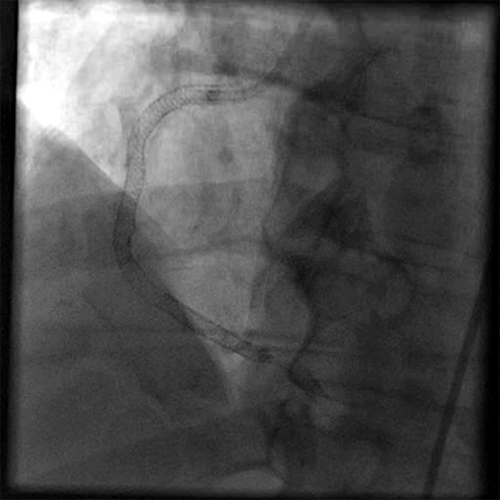

Following PTCA with stenting, final TIMI flow was 3; final thrombus grade was 0 (Cine 4: Final Result Post Definitive Treatment).